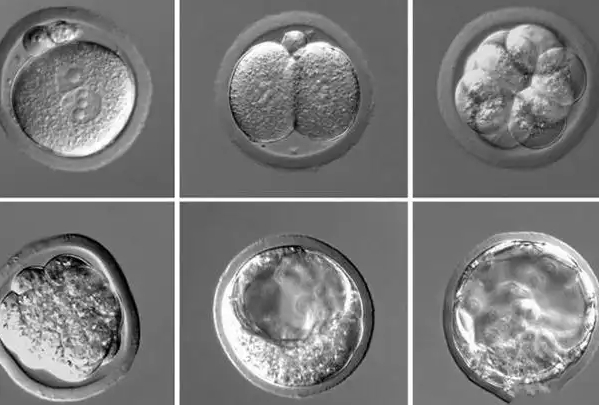

第一,按发育阶段分。 囊胚从早期到扩张,有1到6个阶段。比如,1级是早期囊胚,细胞开始分化;3级是扩张囊胚,体积变大;5级是孵化中囊胚,准备植入子宫。阶段越高,通常意味着发育越成熟,但不是说等级越高就一定好,还得看其他方面。

第二,按内细胞团(ICM)评分。 内细胞团是未来发育成胎儿的部分,评分从A到C。A级表示细胞多、排列紧密;B级是中等质量;C级则细胞少、松散。A级当然最理想,但B级也有成功案例,医生会根据整体情况判断。

第三,按滋养层(TE)评分。 滋养层是囊胚的外层,将来形成胎盘,评分也是A到C。A级代表细胞多、形态好;B级尚可;C级较差。滋养层质量影响植入和营养供应,所以它和内细胞团一起,决定了囊胚的综合等级。

综合起来,常见的囊胚等级像是“3AA”、“4BB”这样的组合,第一个数字是发育阶段,后两个字母分别是内细胞团和滋养层评分。比如,4AA就是扩张囊胚,内细胞团和滋养层都是A级,算得上“优等生”了。但别忘了,等级只是参考,实际选择还得结合遗传检测结果和个体情况。